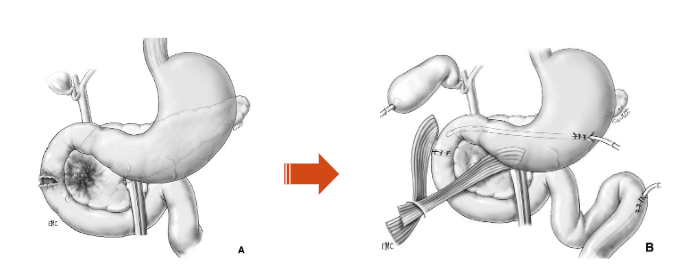

Phẫu thuật loại trừ môn vị – Pyloric exclusion procedure

Vỡ tá tràng, vỡ tuỵ không tổn thương ống tụy chính được điều trị bằng khâu tá tràng, khâu tuỵ, mở thông tá tràng qua Kehr, khâu môn vị, nối vị tràng, hút dạ dày qua dẫn lưu (theo Kenneth D. Boffard và Adam J.Brooks – 2000)

Kỹ thuật đảo dòng tá tràng (túi thừa hóa tá tràng) – duodenal diverticularization procedure

- Khâu tá tràng

- Dẫn lưu mỏm tá tràng

- Cắt hang môn vị, nối dạ dày hỗng tràng

- Cắt thần kinh X

- Dẫn lưu Kehr ống mật chủ

- Đặt hệ thống dẫn lưu cạnh tá tràng đầu tụy

Phẫu thuật loại trừ môn vị